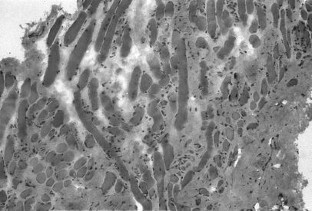

Four patients who presented with congenital restriction of eye movements in association with neurological abnormalities underwent complete ophthalmological examination including electroretinography (ERG) and eye movement recordings. Neurological examinations, neuroradiological studies, muscle histology, chromosomal and genetic linkage analysis were performed.

Fig. 4.